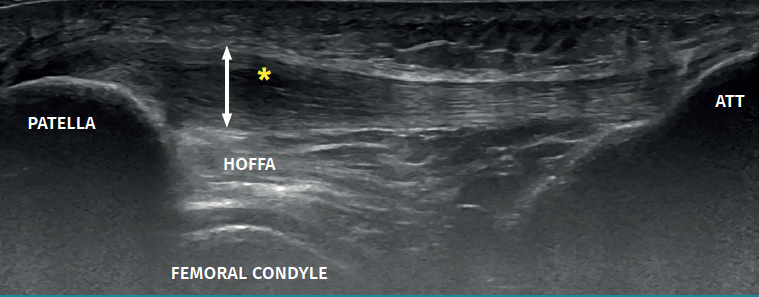

Figure 3. Ultrasound view of proximal patellar tendinopathy with linear probe in craniocaudal longitudinal panoramic view (from left to right). Note the area of decreased echogenicity (hypoechoic), marked with an asterisk, loss of the fibrillar pattern in the deepest and proximal region of the tendon secondary to disruption of the collagen bands, and anteroposterior 8.5 mm thickening (double arrow). ATT: anterior tibial tuberosity.

The ultrasound study of a damaged tendon evidences hypoechogenicity and loss of the fibrillar pattern, the appearance of disorganised connective tissue, and thickening of the tendon (Figure 3). In some cases we observe well delimited hypoechoic images indicating intra-substance rupture with nodular or fibrillar shapes, commonly manifesting in the deepest zone of the tendon in the lower pole adjacent to the patella (Figure 4).